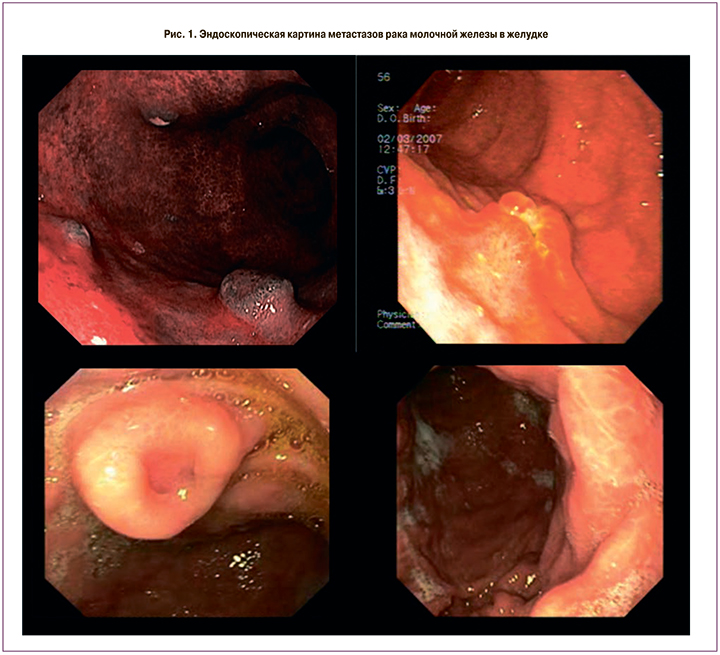

Эндоскопическая картина метастаза РМЖ в стенке желудка визуально проявляется в виде двух основных форм – узловой и инфильтративной (рис. 1). При узловой форме метастатический очаг выглядит как неподвижное, плотное бляшковидное или узловое образование с мелкобугристой поверхностью неоднородной окраски, с эрозированным или изъязвленным участком в центре и перифокальной инфильтрацией у основания. Он может быть единичным, однако могут выявляться несколько участков метастатического поражения стенки желудка.

При инфильтративной форме эндоскопическая картина характеризуется наличием плоского или слегка конусовидно возвышающегося участка плотной неподвижной слизистой оболочки с мелкозернистой или гладкой поверхностью. При осмотре в узкоспектральном режиме выявляется ее аморфный характер с потерей характерного для данного отдела желудка ямочного и сосудистого рисунка, что характерно для злокачественного опухолевого процесса. Размеры участка инфильтрации могут быть весьма вариабельными – от небольших до весьма обширных, захватывающих несколько отделов желудка. В последнем случае эндоскопическая картина становится характерной для диффузно-инфильтративного рака желудка с функциональными нарушениями и деформацией и стенозированием просвета. Окончательный диагноз может быть установлен только на основании результатов морфологического исследования.